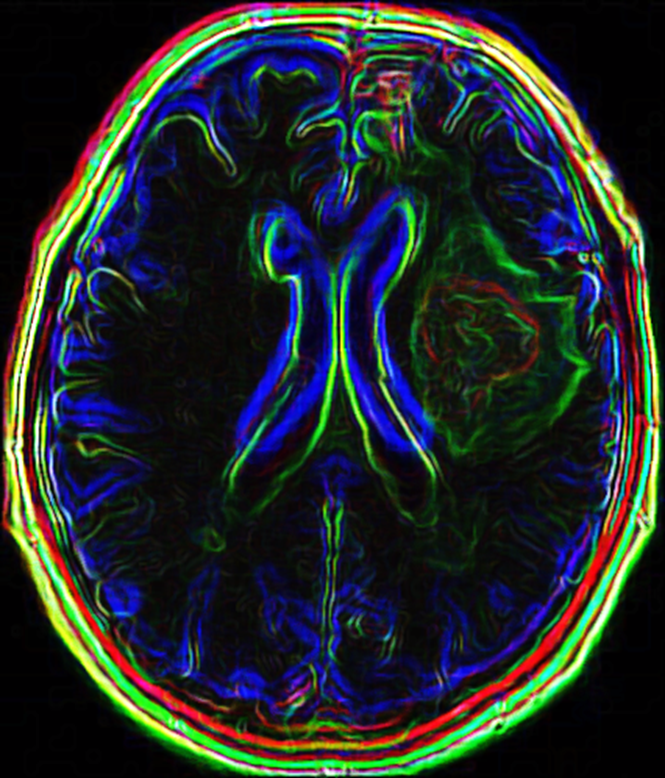

AI 기술과 고해상도 MRI 영상이 결합되어, 기존보다 정밀하게 종양의 유전자 변이(IDH, MGMT 등) 여부를 예측할 수 있게 되었습니다. 이를 통해 생검 없이도 환자의 예후를 판단하고, 맞춤형 치료 전략을 수립할 수 있습니다.